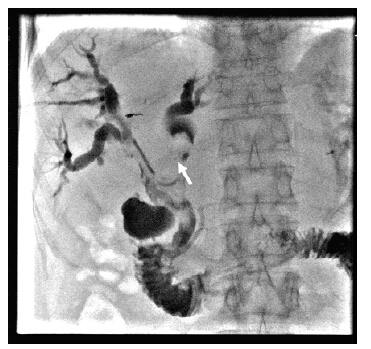

李勇:总体来说, PTCD的普适性较好, 若ERCP失败后仍可选择行PTCD治疗。因此针对该患者我们选择的是先行PTCD处理治疗。从图2的患者术中胆道造影图像可见:左肝内胆管扩张, 呈藤蔓状改变, 右肝胆管、胆总管未见造影剂充盈。左右肝管汇合区及胆总管上段见巨大充盈缺损, 相对应胆管不规则扩张, 少许造影剂可进入十二指肠。根据患者病例特点及影像学资料, 可诊断为局部肿瘤复发合并胆道癌栓形成。